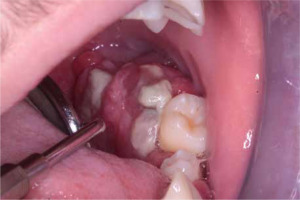

When he was 5 years of age the intraoral examination revealed incomplete primary dentition with five missing teeth, marginal gingivitis, interdental papilla hypertrophy, carious lesions in seven primary teeth, and one permanent tooth of various degrees of advancement for conservative treatment (Fig. 1). The patient was qualified for simultaneous dental treatment under general anesthesia. A panoramic radiograph picture was taken showing the advanced destruction of the alveolar bone in the maxilla and the alveolar part of the mandible. Three primary teeth were completely devoid of bone base. The roots of the lower incisors were only half of their normal length (Fig. 2). Under antibiotic protection (amoxicillin with clavulanic acid at a dose of 30 mg/kg), professional removal of dental plaque and conservative treatment of teeth extraction of four primary teeth with complicated caries and periodontitis were performed. The patient was provided with permanent dental care.